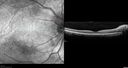

Grade 4 hypertensive retinopathy444 views55 year old man Hhe did have headaches a few weeks ago and also some nausea and vomiting. He noticed for a few weeks the vision in the left eye was blurred and that the vision in the left eye is dark.

VA OD: Dcc20/20

VA OS: Dcc20/100-1

He was admitted directly to ICU for blood pressure control (290 / 170 mmHg)

3 weeks later his VA increased to 20/20 OD, 20/32 OSJan 29, 2019